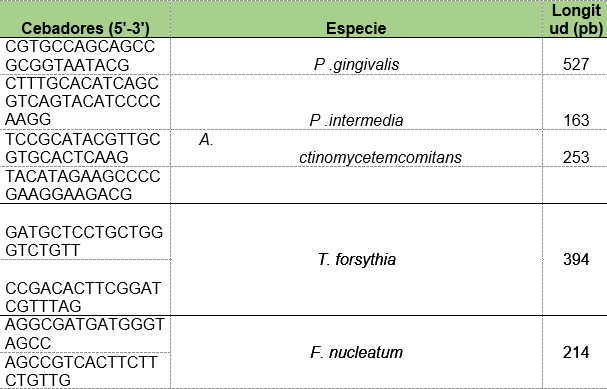

Se realizaron PCR con cada par de oligonucleótidos utilizando los genomas extraídos de la cepa silvestre. Los cebadores utilizados para la detección de las especies bacterianas A. actinomycetemcomitans, P. gingivalis, P. intermedia, T. forsythia y F. nucleatum fueron los que se muestran en la Tabla 1. Las condiciones de las PCR multiplex para la detección de estos microorganismos se muestran en las Tablas 2 y 3.

Tabla 1: Diseño de cebadores para la detección de las especies bacterianas presentes en las muestras periodontales